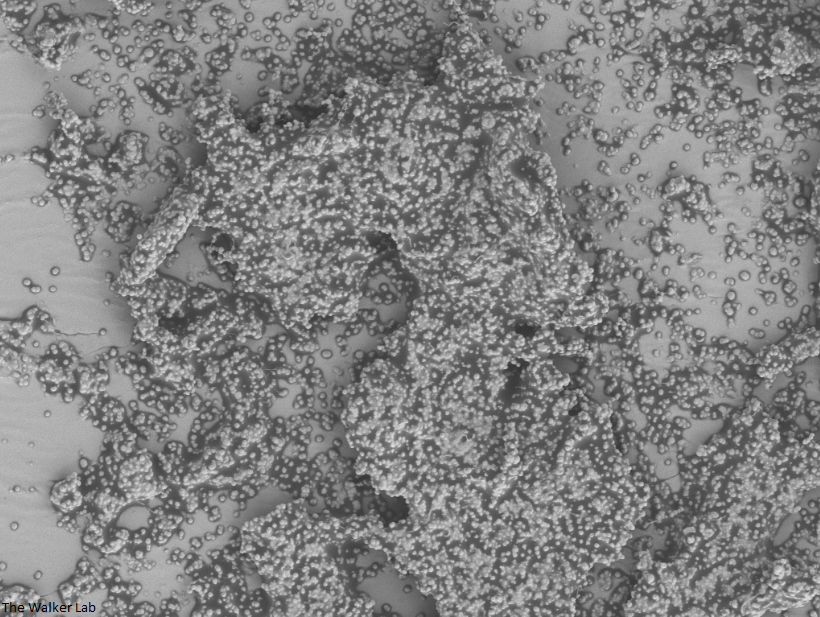

Bladder Epithelial Cells